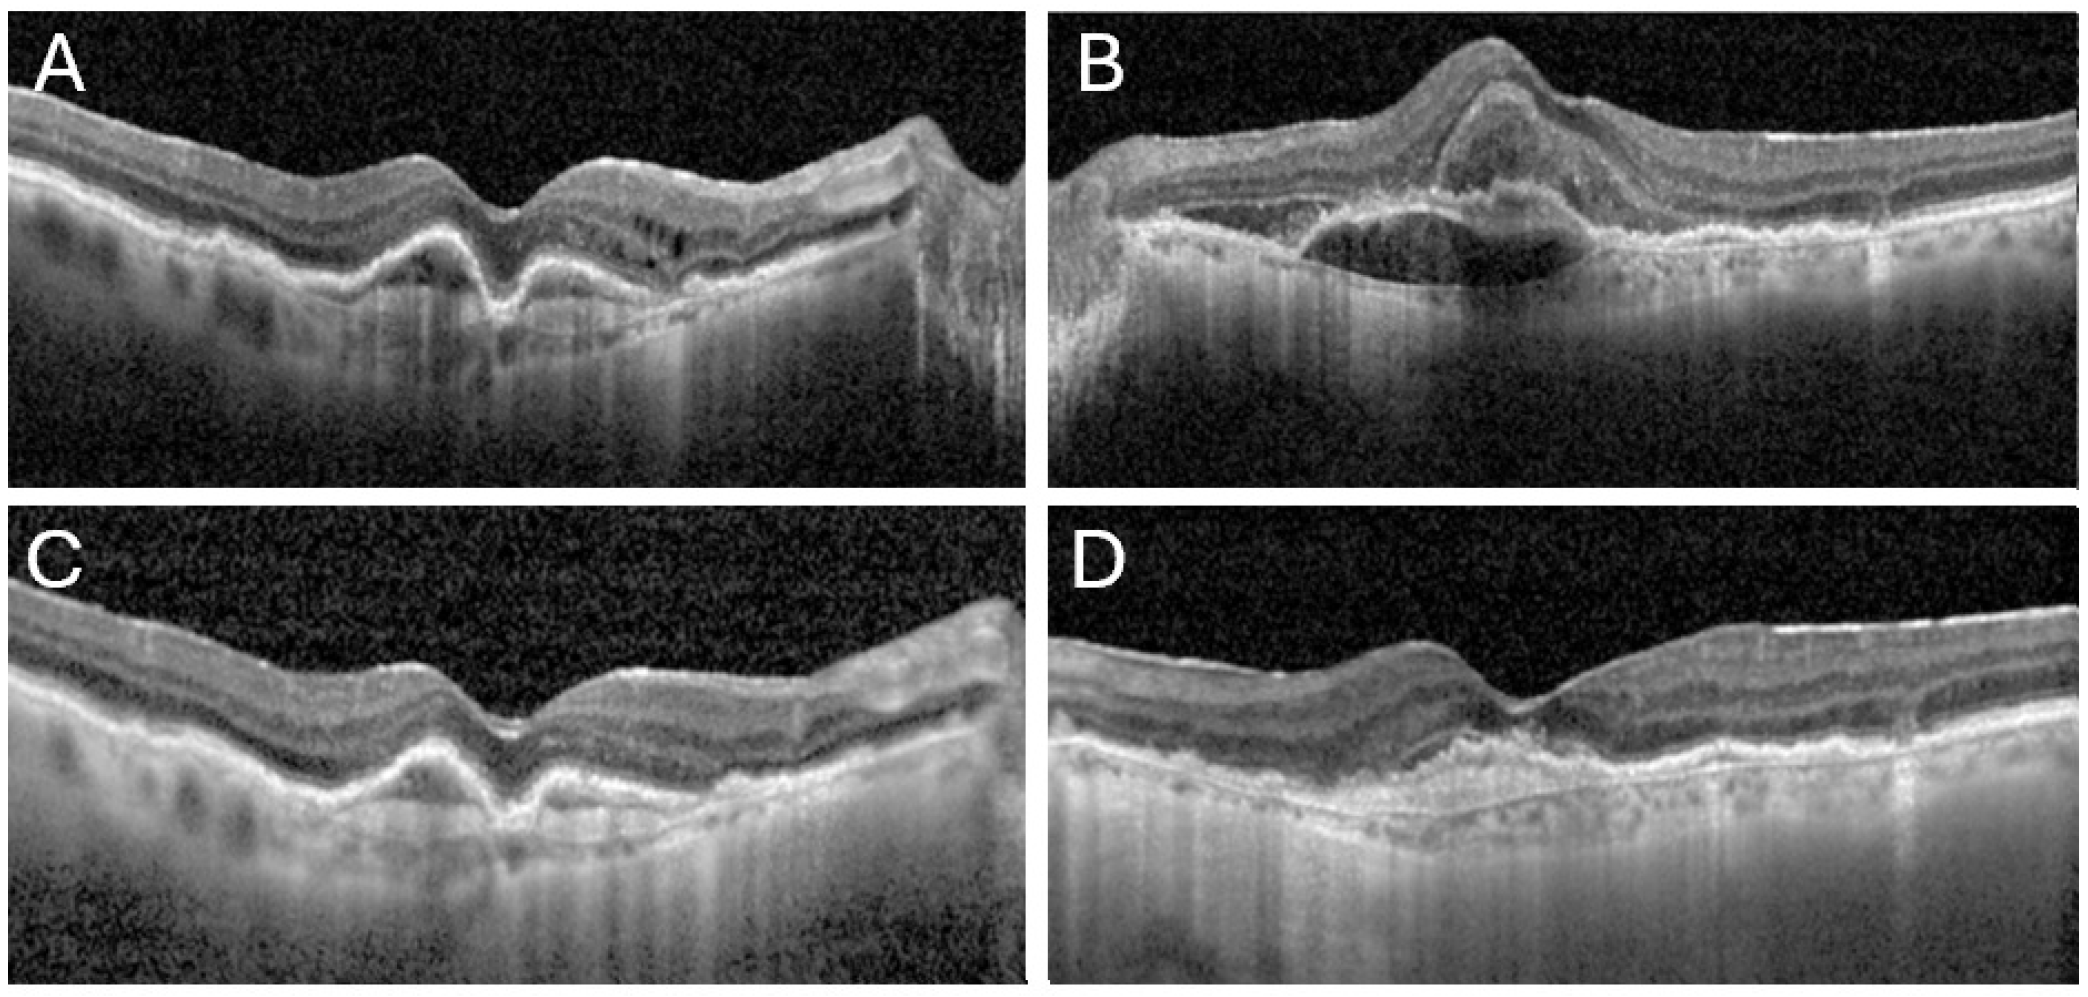

2. Case Report